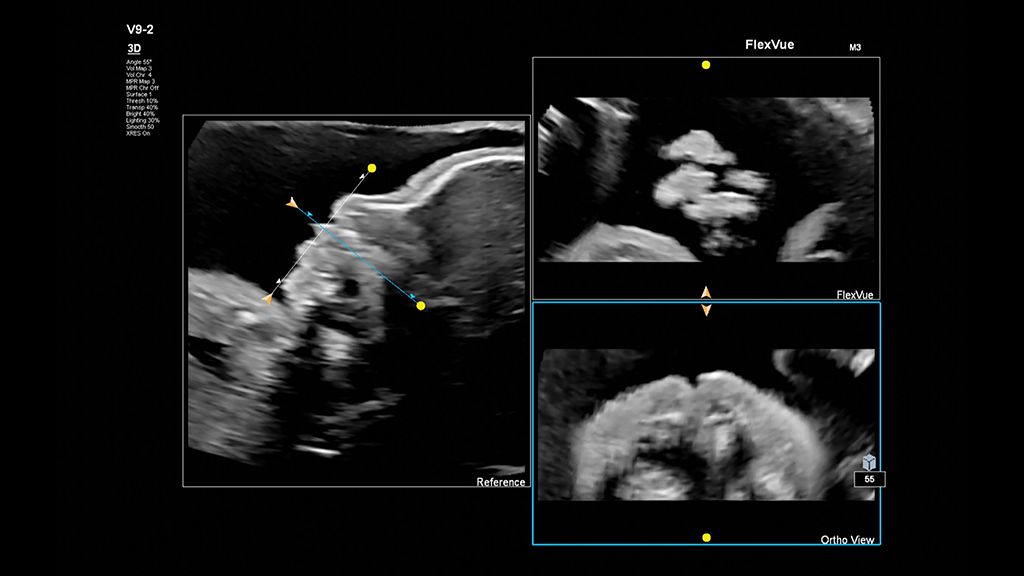

Demonstrated results using FlexVue

It (FlexVue) takes all of the complications out of MPR and manipulation of a surface-rendered volume. By deploying a straight line or a curved trace or continuous trace, we can take a curved image, flatten it out and make it a single planar image.